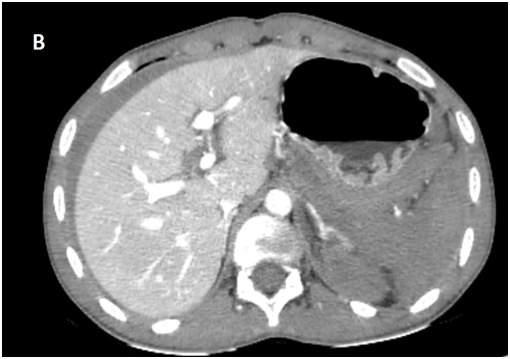

Whole body CT Scanner was performed 5hours after the accident Figure 1, which revealed a laceration fracture of the spleen responsible for a low abundant intraperitoneal hematoma, associated with left renal ischemia due to a sub intimal damage on the left renal artery wall, with formation of a secondary obstructive thrombus, in addition to a left peri-renal hematoma of 16mm, without parenchymal lesions or extravasation of contrast, otherwise ; left vein, the right kidney and his pedicle were intact.

Figure 1A Contrast enhanced CT abdominal scan.

Figure 1B Contrast enhanced CT abdominal scan.

Figure 1C Contrast enhanced CT abdominal scan.

Figure 1D Late acquisition of contrast enhanced CT abdominal scan.

laceration fracture of the spleen responsible for a low abundant intraperitoneal hematoma, associated with left renal ischemia due to a sub intimal damage on the left renal artery wall, with formation of a secondary obstructive thrombus, in addition to a left peri-renal hematoma of 16mm, without parenchymal lesions or extravasation of contrast, otherwise ; left vein, the right kidney and his pedicle were intact.

A Contrast enhanced computed tomography control was performed at D+7 showing a sudden stop of the Contrast progression at the initial portion of the left renal artery, leading to total left renal ischemia, with stability of the perirenal hematoma, spleen injury and no extravasation at the late acquisitions.